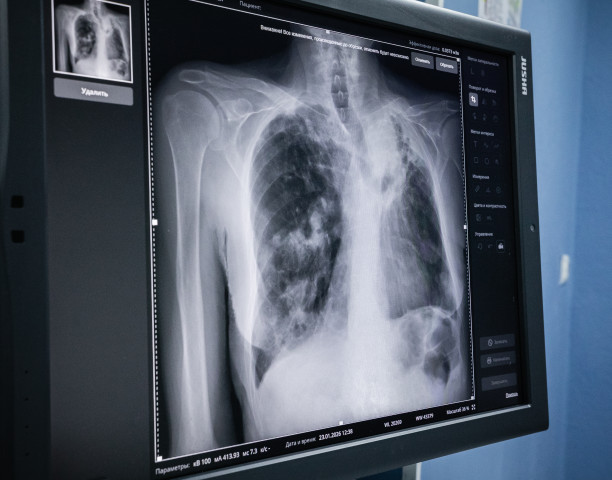

Мужчина решил планово пройти диспансеризацию в поликлинике. По результатам флюорографии его решили отправить на компьютерную томографию. После уточняющей диагностики у онколога медики смогли обнаружить в легком злокачественную опухоль размером порядка 5 сантиметров.

ФОТО Алексея АНДРОНОВА